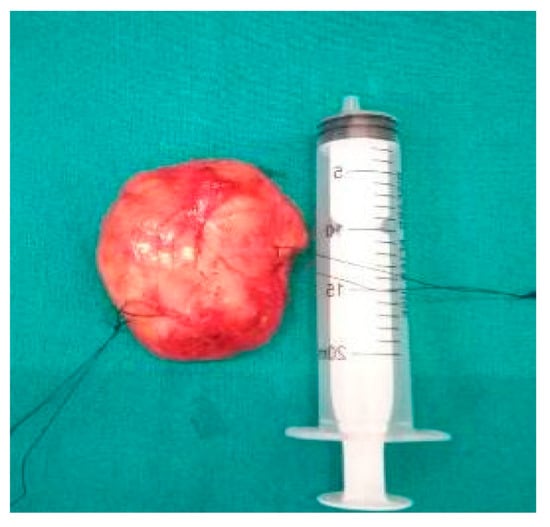

6. Differential Diagnosis of the Extracranial FNS

7. Therapeutic Strategies in the Management of FNS Extracranial Segment